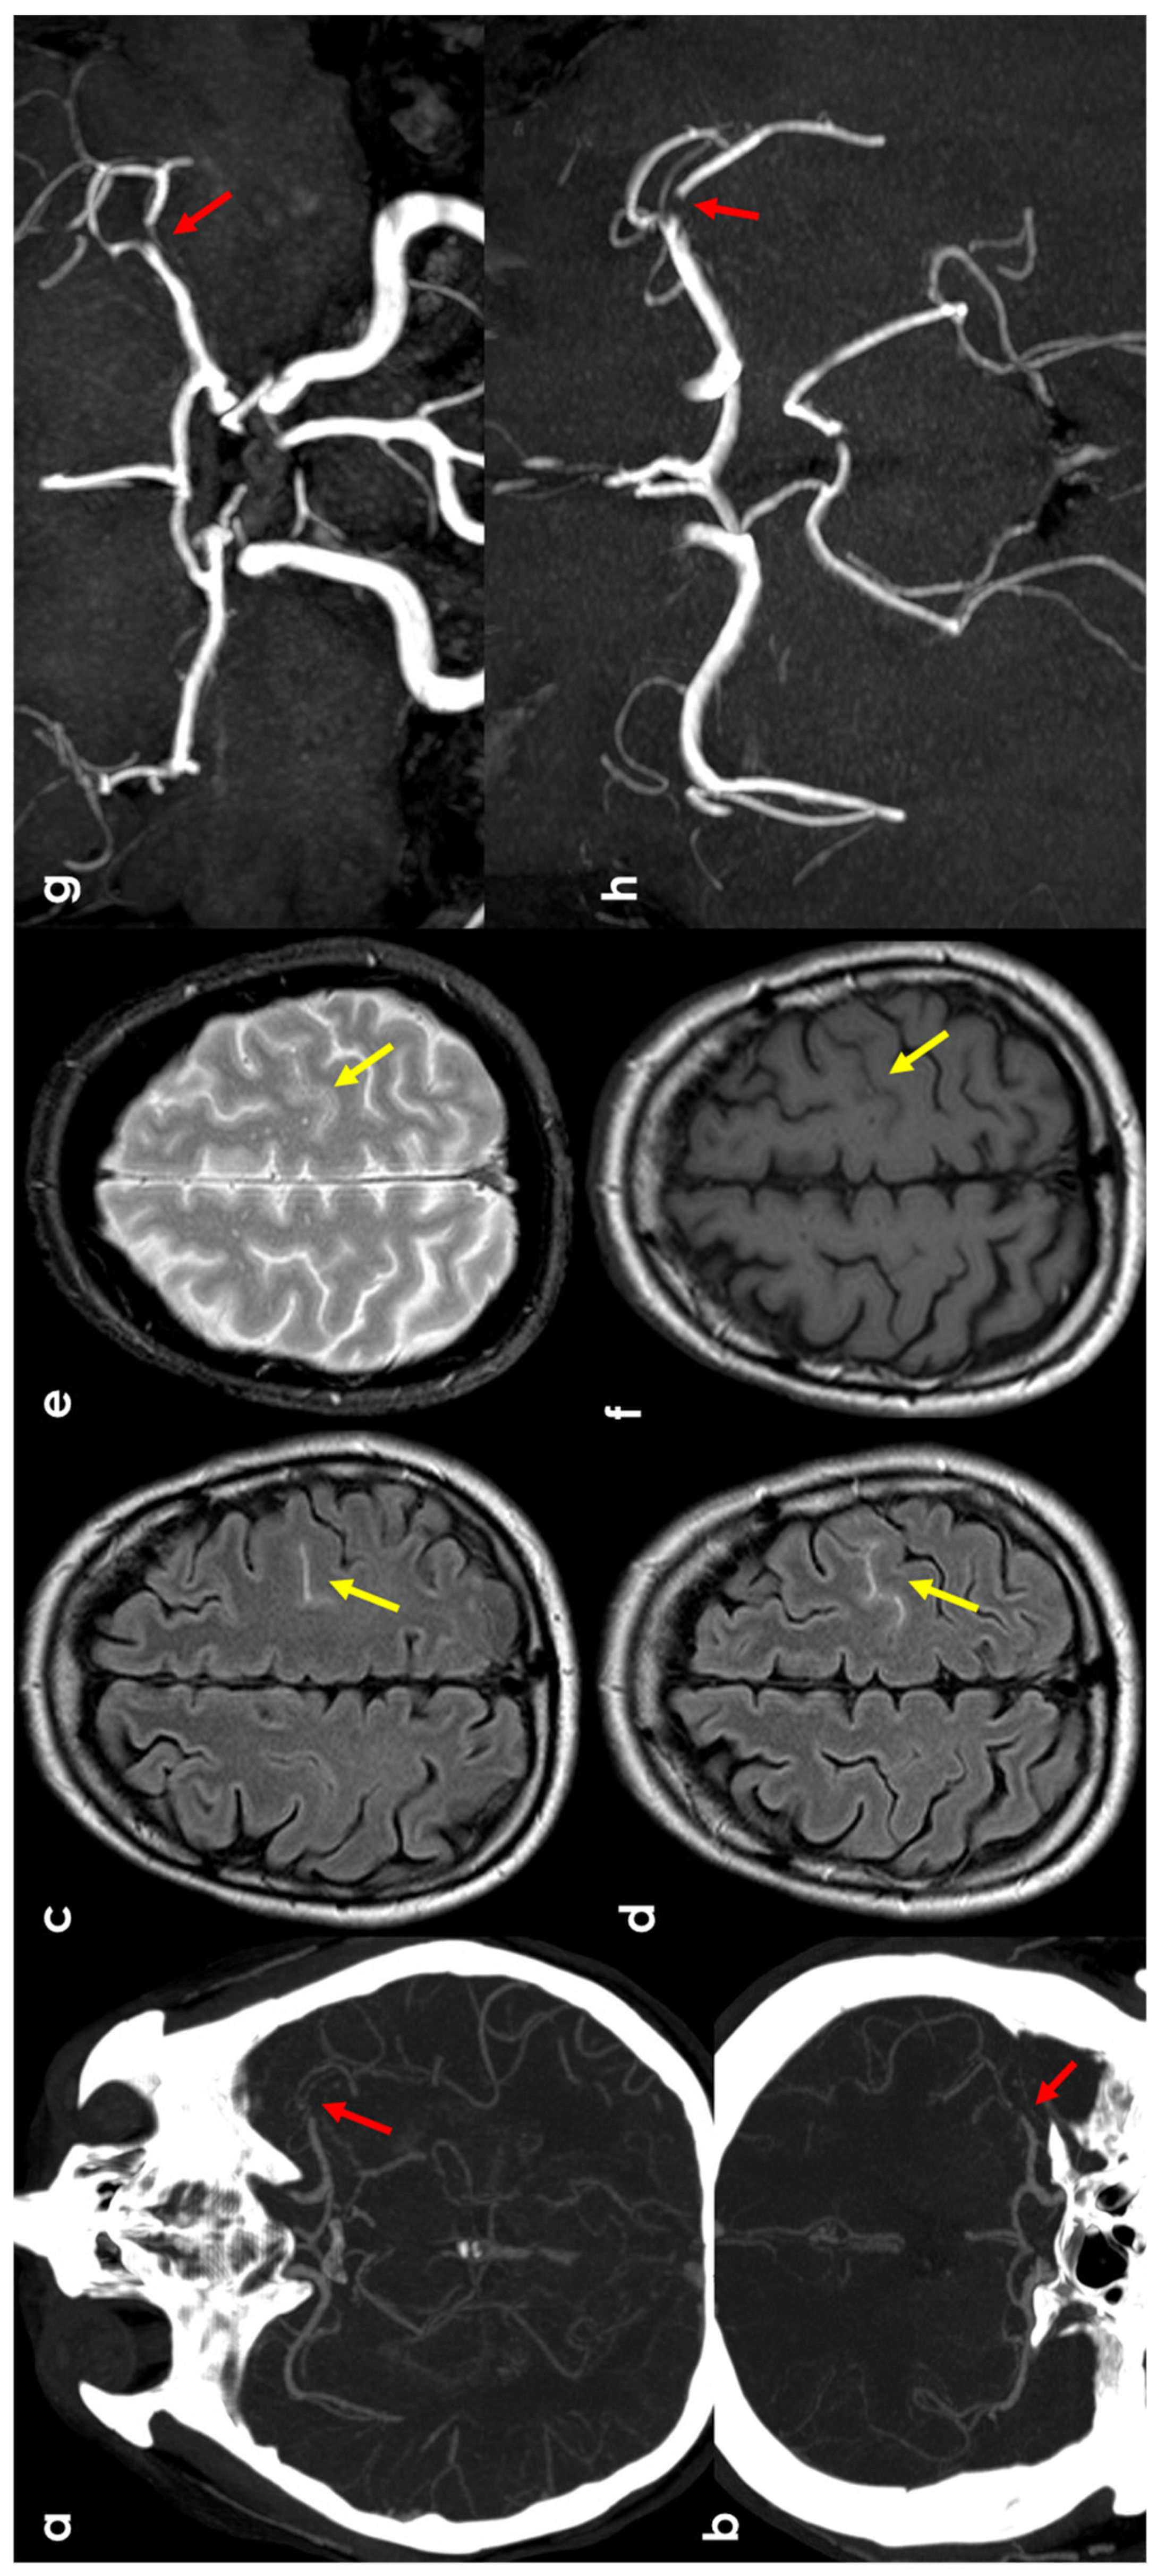

3.2. Hemodynamic Arterial Stenosis

3.6. PRES/RCVS